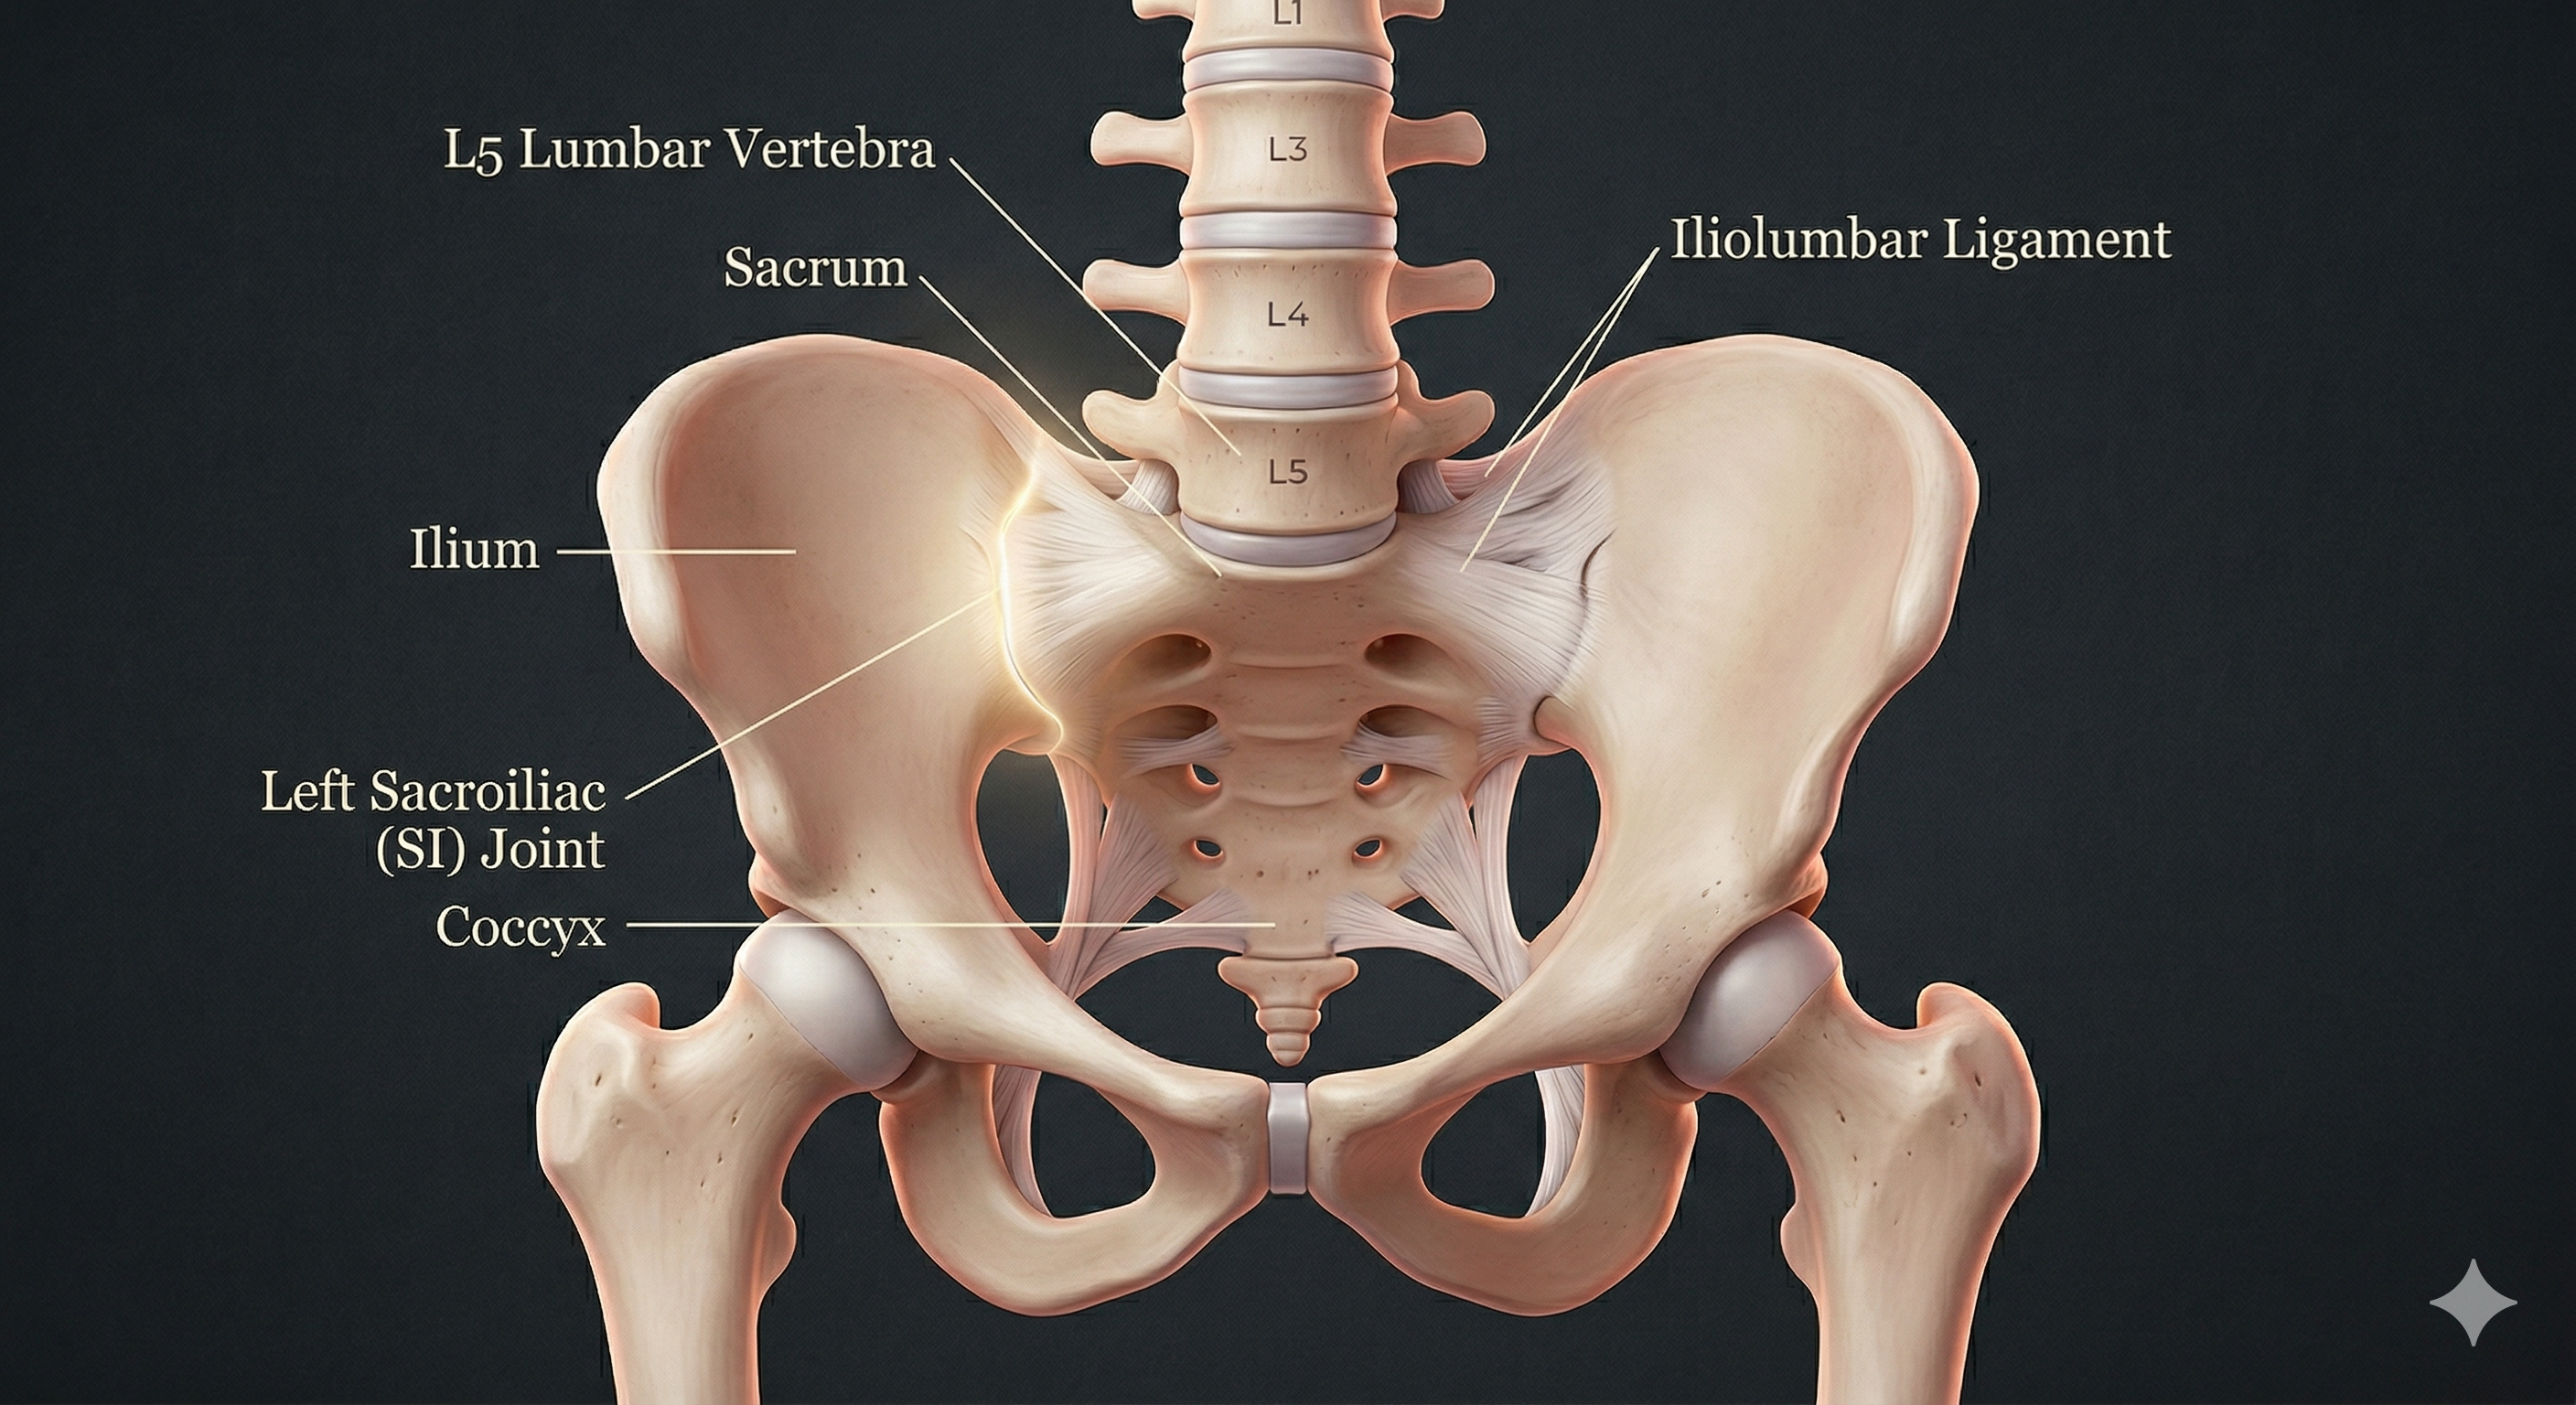

The Sacroiliac (SI) Joint is the critical intersection where your spine meets your pelvis. Unlike the shoulder or hip, the SI joint is not designed for wide-range movement; it is a "shock absorber" that relies on friction and tight ligamentous support to stay aligned.

When hormonal shifts introduce laxity into this anchor point, the joint can undergo "micro-misalignments." These tiny shifts trigger a cascade of protective muscle guarding in the glutes, hamstrings, and lower back. This is why many women feel like they need to stretch their hamstrings constantly—not because the muscle is short, but because it is trying to stabilize a "wobbly" pelvis.

Imagine your pelvis as the center of a clock. Instead of trying to reach for "12" or "6," focus on drawing everything in toward the center point. This "hugging of the bone" protects the nerves exiting the sacrum and prevents the inflammation of the mucosal lining within the joint itself.